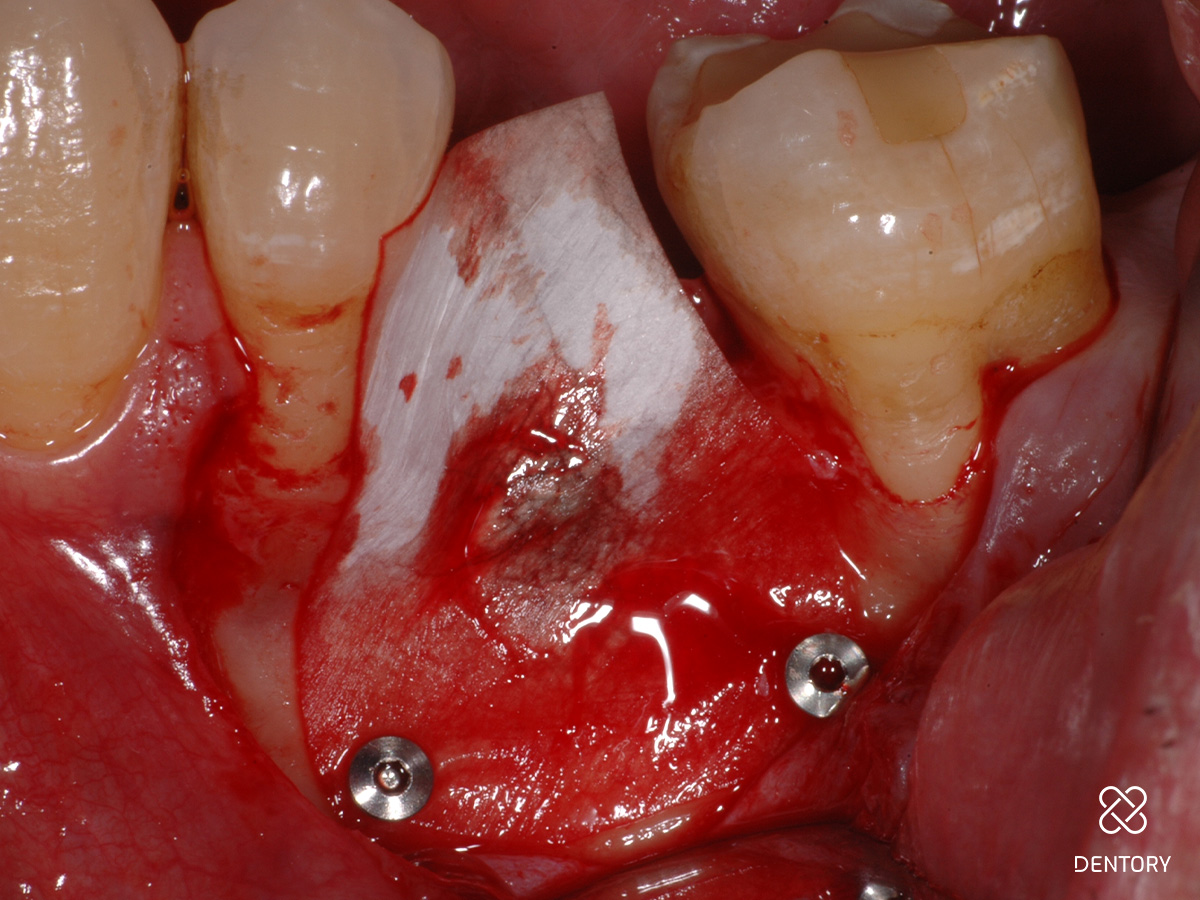

Abbildung 5

Die zugeschnittene Perikardmembran wird apikal mit zwei Pins fixiert; dies dient der Stabilisierung des Augmentats und erleichtert das klinische Arbeiten.